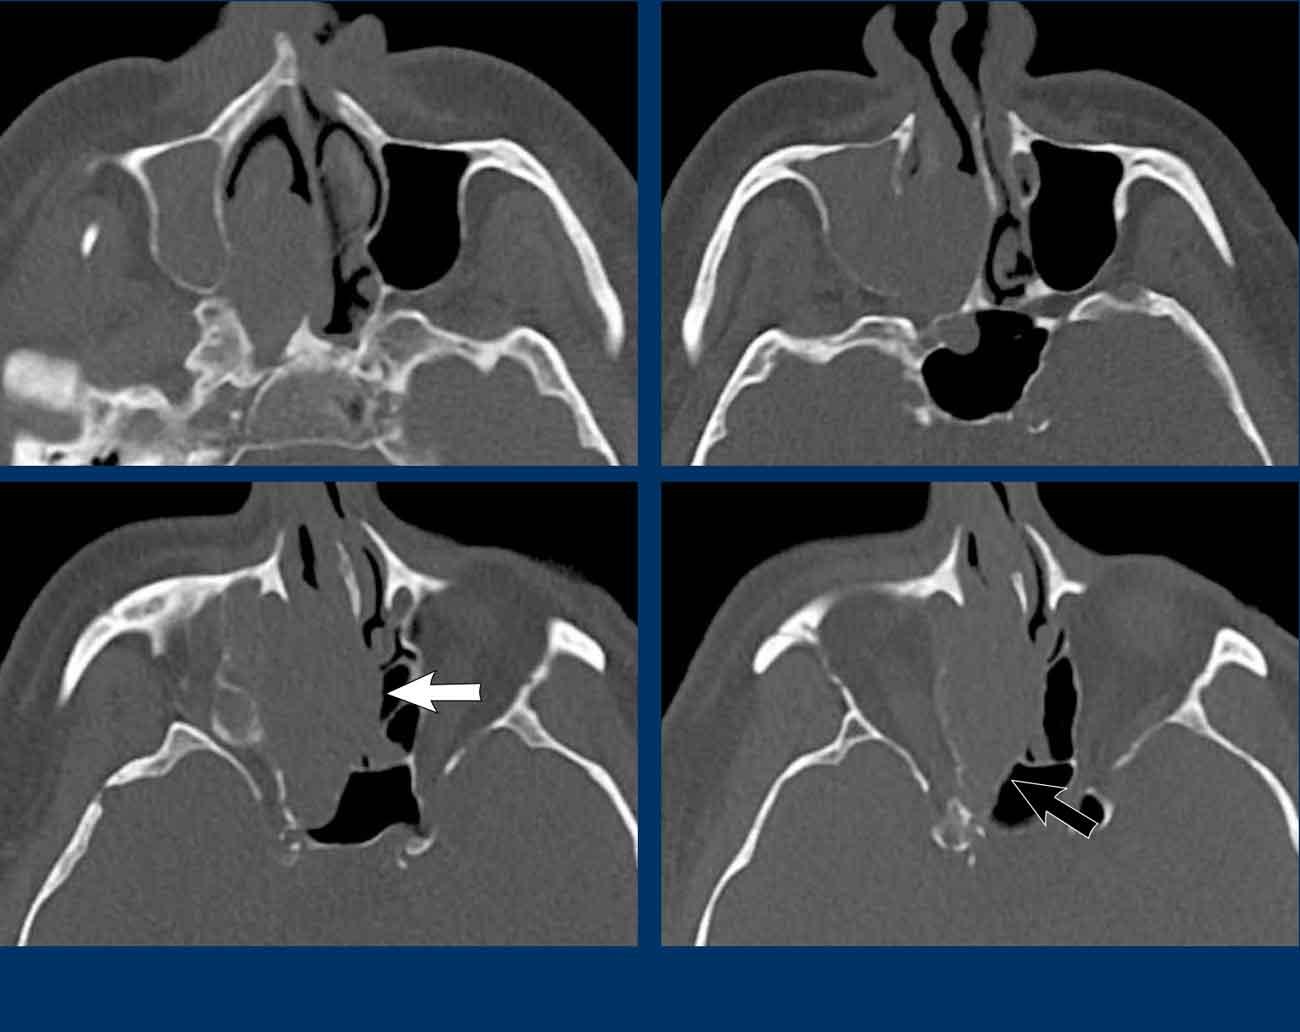

Hai dấu hiệu cảnh báo là:

- Phá hủy thành trong xoang hàm (mũi tên đen) và vách mũi (mũi tên trắng).

- Bệnh lý hoàn toàn một bên.

Ở bệnh nhân viêm mũi xoang, có thể có giãn rộng và đôi khi thậm chí phá hủy xương, nhưng bệnh lý (hầu như) luôn luôn xảy ra hai bên.